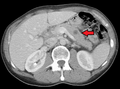

CT image of multiple liver metastases